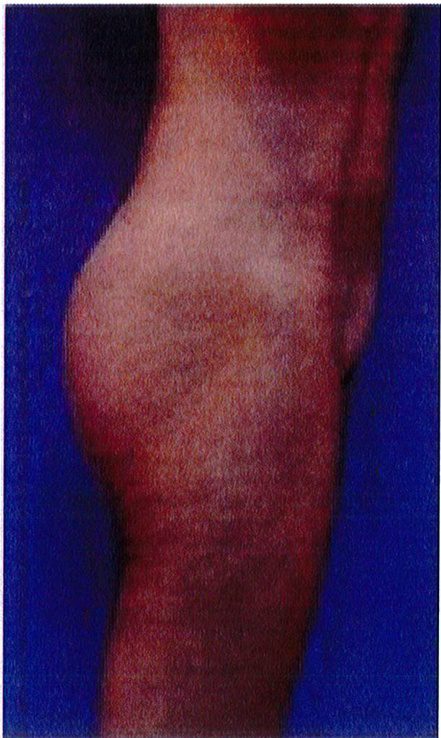

Hình. 18.. (A) Hình anh trước và (B) và sau phẫu thuật làm đầy mông của bệnh nhân được đặt khối implant dưới cân thể tích 225 mL, hai bên.

Bệnh nhân 31 tuổi tiền sử khỏe mạnh, có chỉ định nâng mông bằng implant do thiếu hụt thể tích. Hai khối anatomic implant 225 mL polyurethane dạng gel được đặt ở vị trí dưới cân. Sau phẫu thuật không ghi nhận biến chứng trong suốt quá trình hồi phục, vết mổ liền tốt (Hình 18).